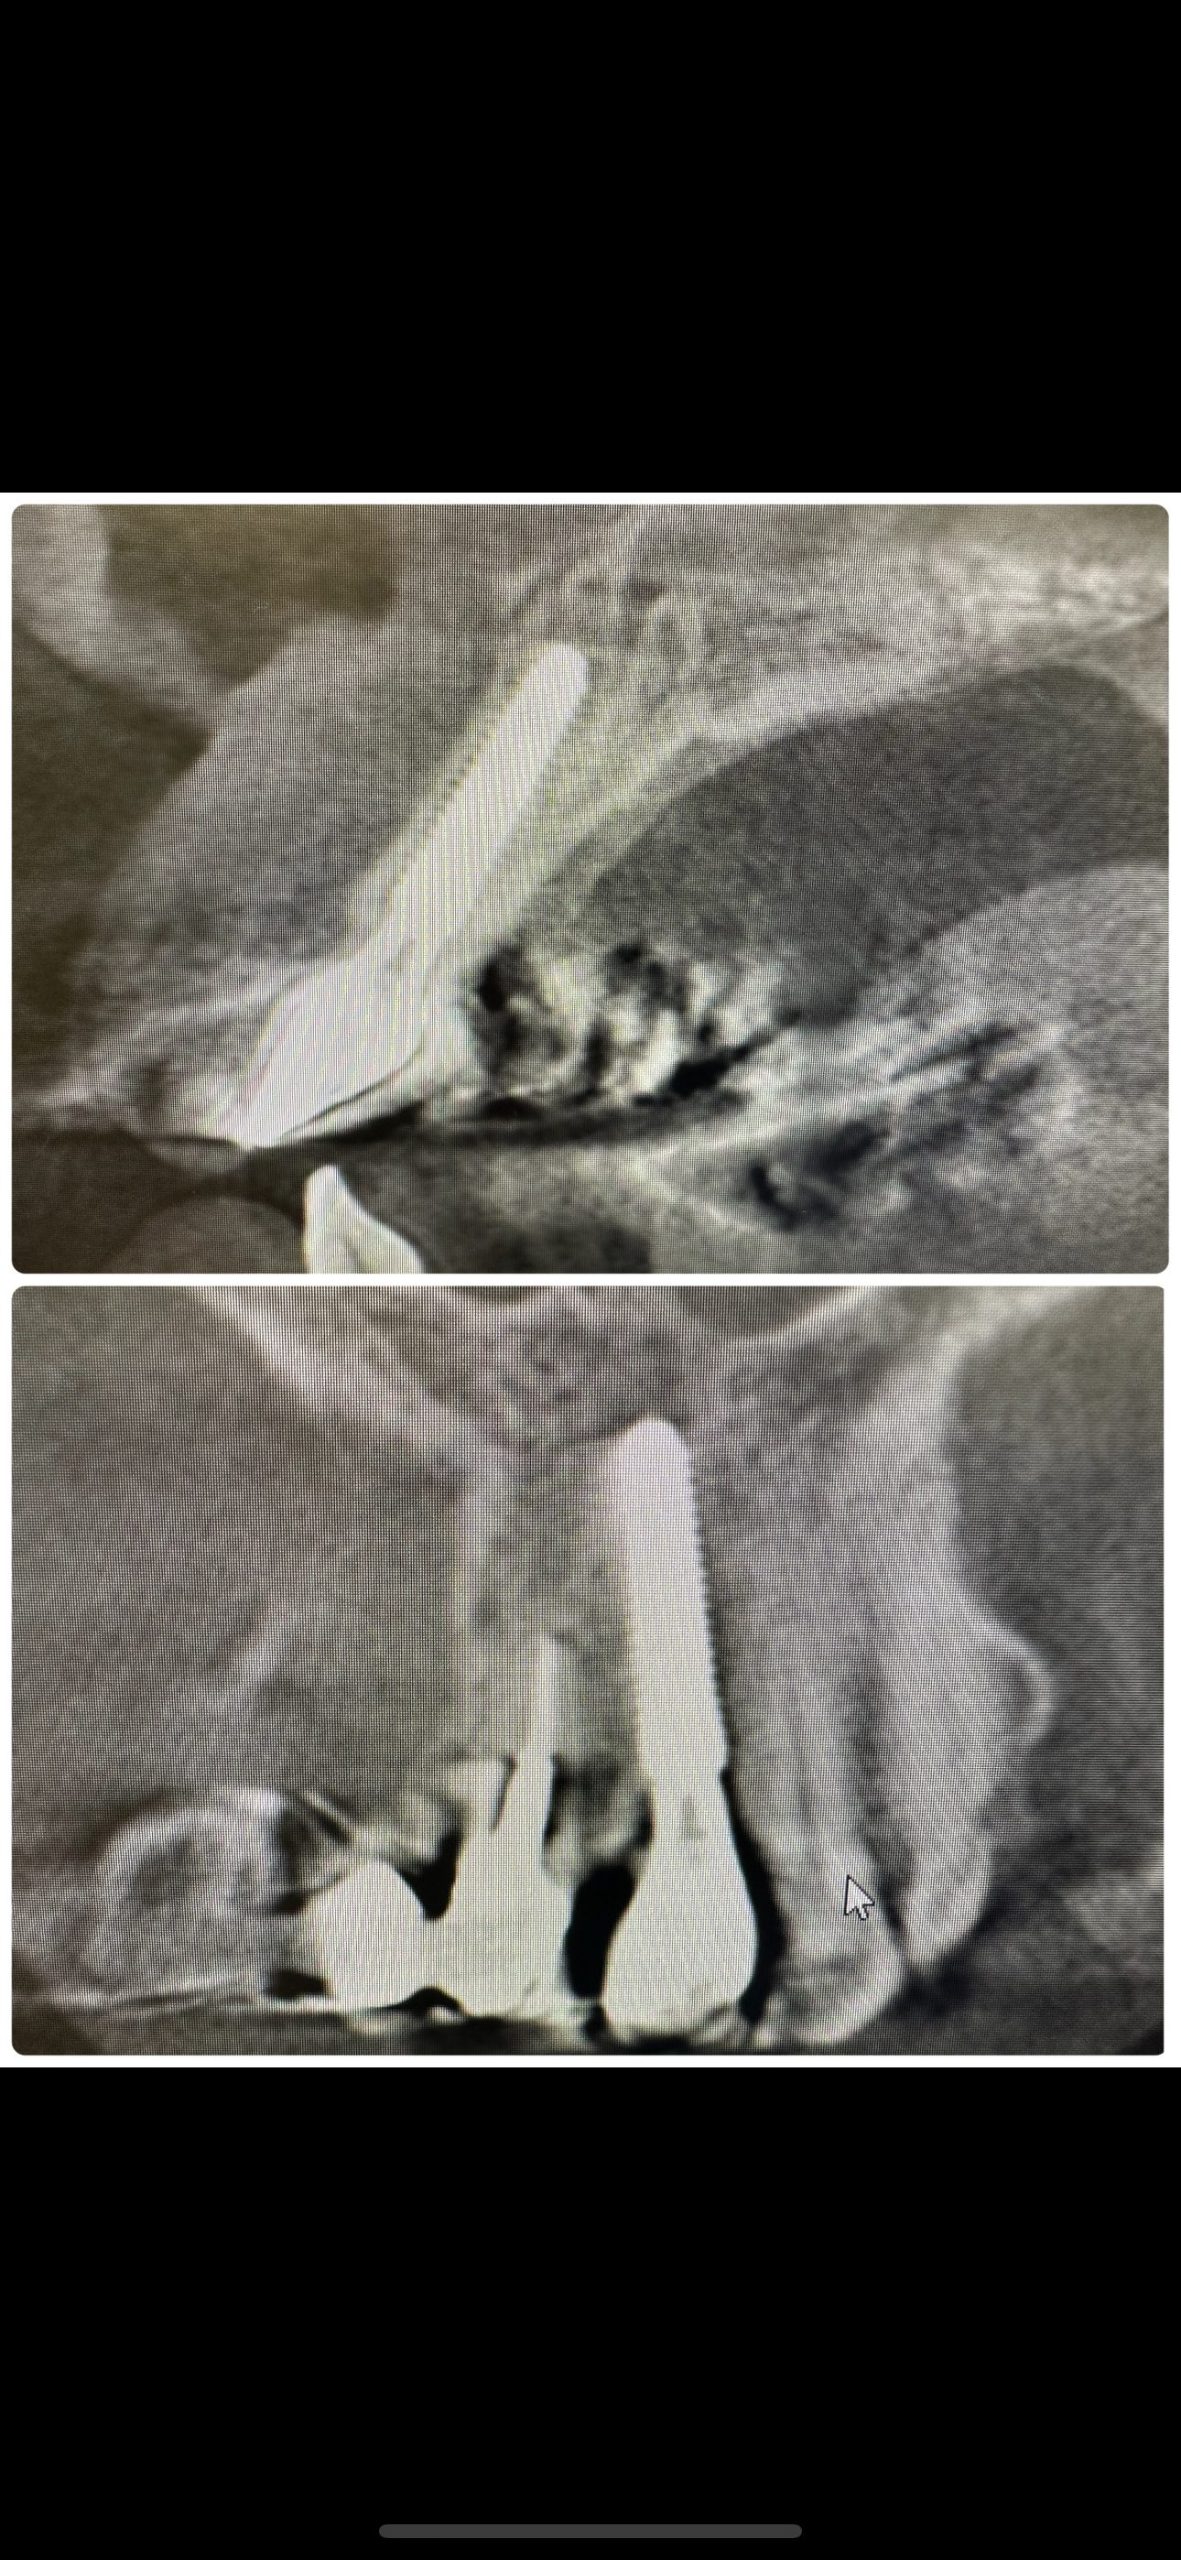

次はインプラント関係

オペ後3ヶ月経過、本日増す締め3回目

最後にCT、トライアングルボーン内に良い角度に埋入されている

オペはいつもフリーハンドです

画像見て、3次元に顎骨形態把握出来る、またメルマーク沢山あるので見逃さないのがコツかな💪

ナイフスレッド径4.0 長さ18ミリ プラットフォームスイッチング、モーステーパージョイント